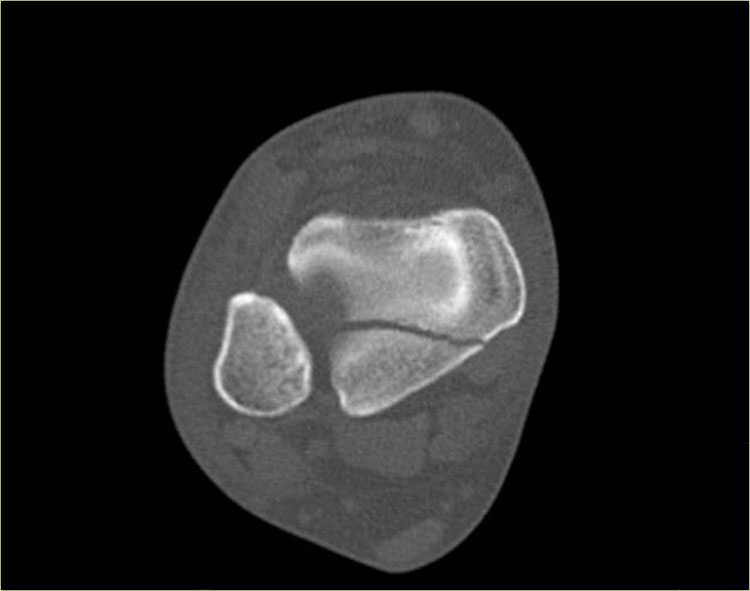

Hãy quan sát các hình ảnh và sau đó cuộn sang hình ảnh tiếp theo.

Đường gãy qua đầu xương có thể dễ bị bỏ sót (mũi tên xanh).

Đường gãy qua tấm sụn tiếp hợp chỉ được phát hiện trên CT.

Tiếp tục xem các hình ảnh CT.

Các hình ảnh CT thể hiện rõ ràng đường gãy qua tấm sụn tiếp hợp và đầu xương.

Đây cũng là gãy xương Salter-Harris type III.

Lưu ý rằng đồng thời có gãy xương Tillaux.

Chúng ta sẽ thảo luận về các gãy xương này ở phần tiếp theo.